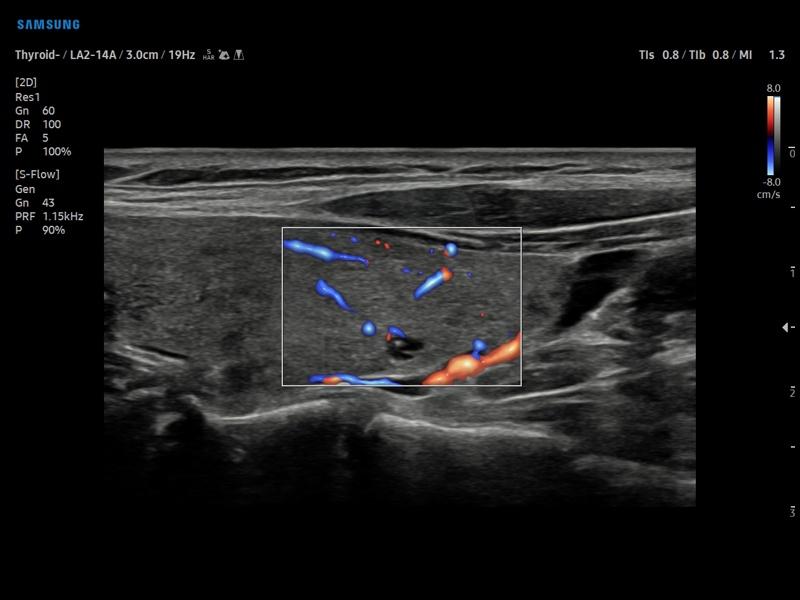

Режим S-Flow - щитовидная железа